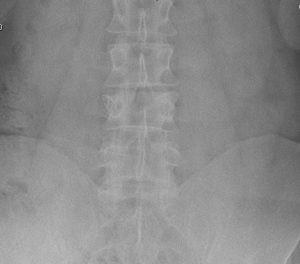

Paciente joven que acude por lumbalgia localizada, mecánica, refractaria a tratamiento médico de >6 meses de duración. Refiere antecedente traumático desencadenante del cuadro (precipitación gran altura). En las pruebas no se aprecia alteración de balance sagital.

Fx unilateral platillo superior L4 derecho, sin desequilibrio coronal